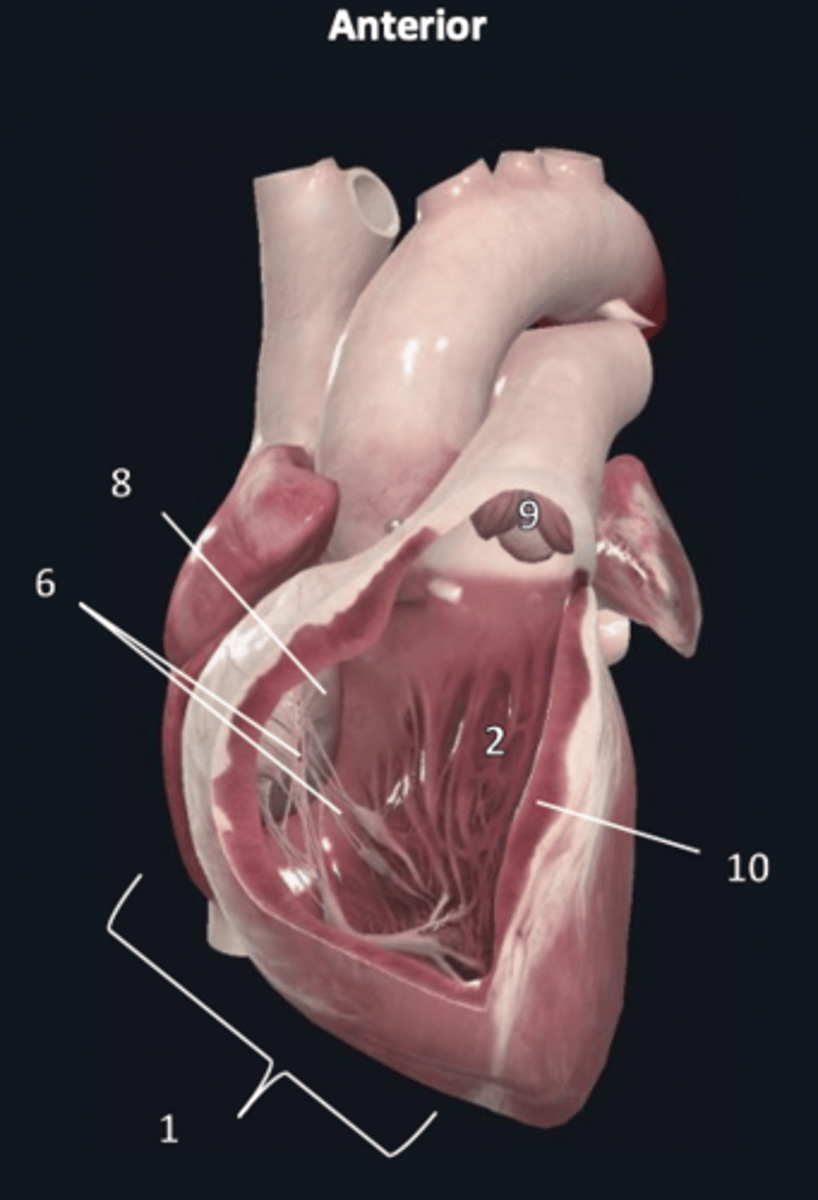

right ventricle

1

trabeculae carneae

2

septal papillary muscle

3

anterior papillary muscle

4

inferior papillary muscle

5

chordae tendineae

6

moderator band

7

tricuspid valve

8

pulmonary semilunar valve

9

interventricular septum

10